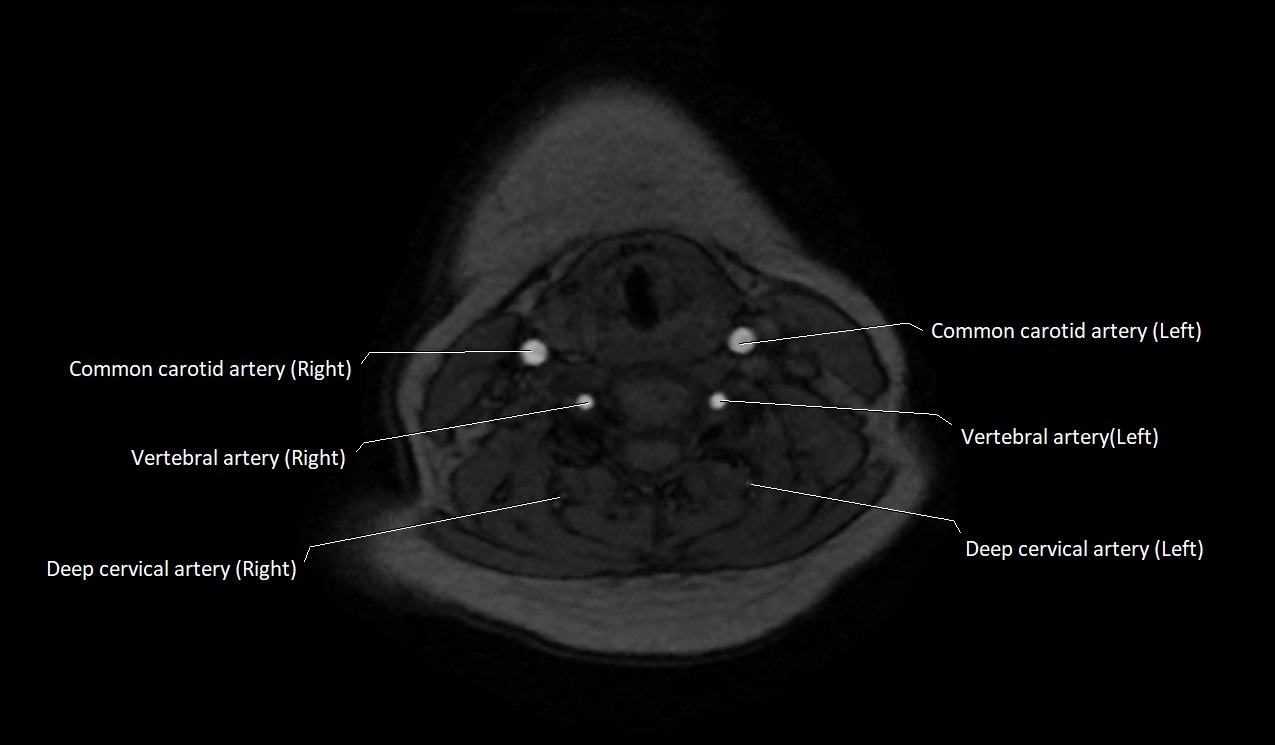

CT image

image